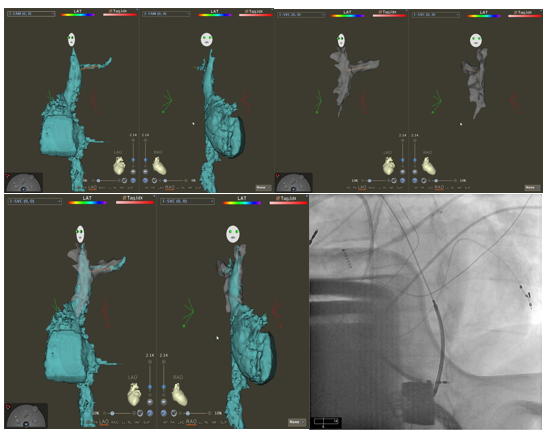

Discussion: An excessively tortuous right axillary vein and SVC were accessed. A DecaNav catheter and CARTO-Merge were utilized to create a 3D map to locate the azygos vein along with overlap of previously obtained CT angiography. A Decanav and Amplatz catheter were alternatively used for access. The defibrillator coil was placed to the level of the diaphragm and sutured to prepectoral fascia. An adaptor was connected to this lead given it was a DF4 device and a coil had to be added to the DF4 lead. The pocket was expanded to accommodate the adaptor and the leads were coiled behind the device. Ensuing DFTs were successful and there were no procedural complications.

Conclusion: This is a case of successful RV coil insertion in the azygos vein via difficult right-sided access utilizing 3D mapping and overlapping CT angiography. At follow-up, impedance in the azygos coil was measured at 65-68 ohm. To our knowledge, the use of 3D mapping has not been previously used in this application and may provide a valuable tool in future cases.